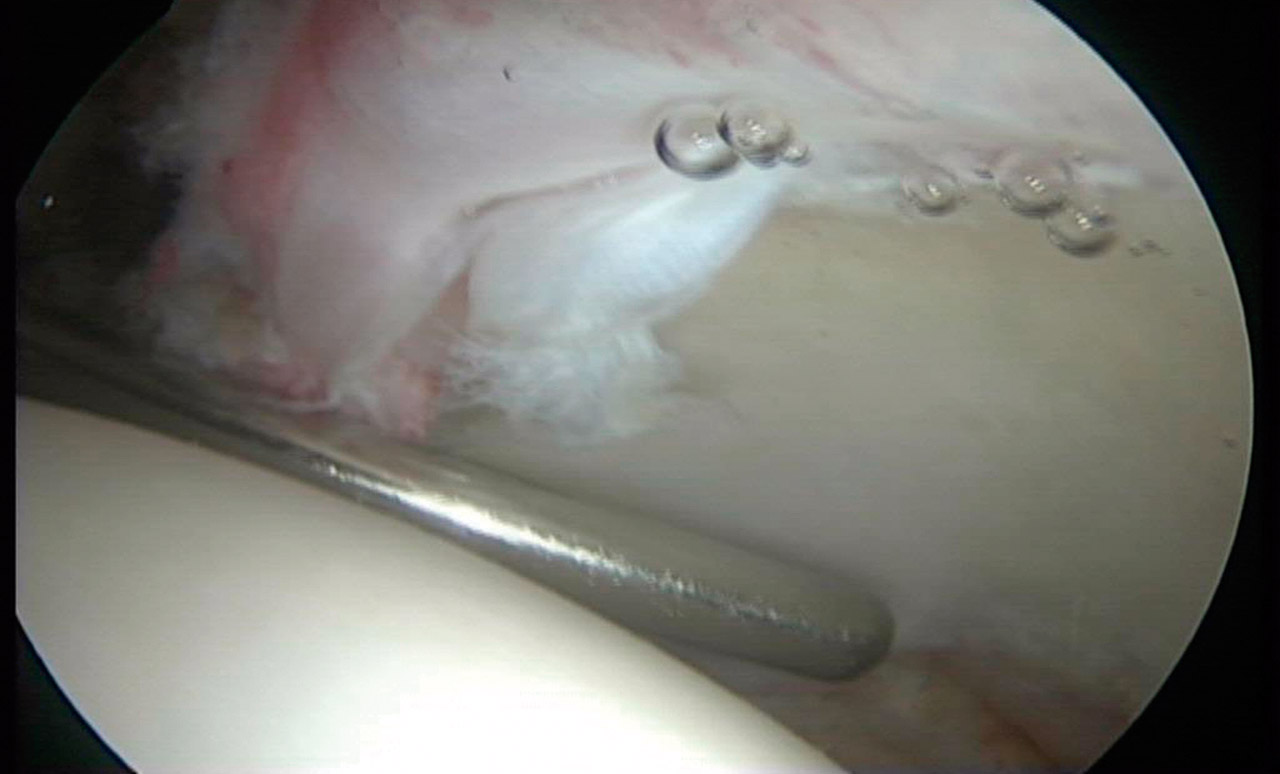

Las cirugías se realizaron con anestesia espinal, según técnica quirúrgica descrita previamente(20). Las lesiones del labrum acetabular se clasificaron según la clasificación propuesta por el grupo Multicenter Arthroscopic Hip Outcome Research Network (MAHORN)(21), que establece 4 categorías: labrum normal, labrum hipoplásico/hiperplásico, rotura del labrum y lesiones intrasustancia del labrum. La rotura del labrum se subclasificaba en rotura compleja degenerativa, separación condrolabral, rotura parcial, rotura completa y lesión de tipo flap, y las lesiones intrasustancia se subclasificaban en mucoide o amarillo, blando, hemático, osificado y calcificado. Para la localización de la lesión se utilizó el método geográfico descrito por Illizaliturri et al.(22).

Artroscópicamente, el tipo de CFA era mixto en 86 caderas (52,7%), de tipo Cam en 67 (41,1%) y de tipo Pincer en 10 (6,2%). El labrum presentaba una morfología normal (Figura 1) en 140 caderas (85,9%), hipoplásico (Figura 2) en 17 (9,8%) e hiperplásico (Figura 3) en 6 (4,3%). Se detectó algún grado de rotura del labrum en 133 caderas (81,6%); de ellas, en 98 caderas (60,1%) eran separaciones condrolabrales (Figura 4), en 26 (15,9%) roturas complejas-degenerativas (Figura 5), en 5 (3,0%) roturas parciales y en 4 (2,4%) roturas completas. El labrum presentaba cambios intrasustancia en 30 caderas (18,4%), distinguiendo en 19 (63,3%) calcificado, 9 (30%) hemático (Figura 6) y 2 (6,6%) mucoide-amarillo.